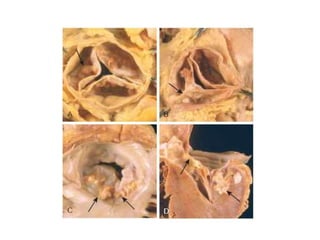

Infective Endocarditis

• Infective endocarditis (IE) is a microbial

infection of the heart valves or the mural

endocardium that leads to the formation of

vegetations composed of thrombotic debris

and organisms, often associated with

destruction of the underlying cardiac tissues.

• Infective endocarditis is classified into acute

and subacute forms based on the tempo and

severity of the clinical course.

• Acute endocarditis refers to tumultuous,

destructive infections, frequently involving a

highly virulent organism attacking a previously

normal valve. It is associated with of substantial

morbidity and mortality, even with appropriate

antibiotic therapy and/or surgery.

• Subacute endocarditis refers to infections by

organisms of low virulence affecting a previously

abnormal heart, especially scarred or deformed

valves. The disease typically appears insidiously

and—even if untreated— follows a protracted

course of weeks to months; most patients

recover after appropriate antibiotic therapy.

Subacute endocarditis

Acute endocarditis

Ring abscess